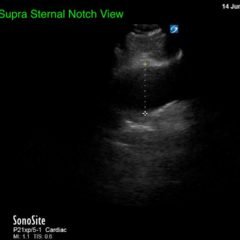

Ventricular Fibrillation - Image

Ventricular fibrillation, vfib

Thoracic Aortic Aneurysm Measured by Point of...